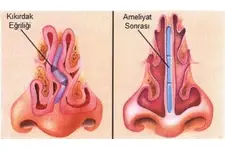

Burun Kıkırdak Eğriliği Belirtileri ve Tedavisi Burun kıkırdak eğriliği, burun septumunun (burun ortasındaki yapı) anormal bir şekilde eğrilmesi veya şekil bozukluğu olarak tanımlanabilir. Bu durum, bireylerin yaşam kalitesini etkileyen ve çeşitli sağlık sorunlarına yol açabilen önemli bir rahatsızlıktır. Burun kıkırdak eğriliği, genellikle doğuştan gelir, ancak travma veya yaralanmalar sonucu da gelişebilir. Burun Kıkırdak Eğriliğinin Belirtileri Burun kıkırdak eğriliği, birçok belirtiyle kendini gösterebilir. Bu belirtiler kişiden kişiye değişebilir, ancak genel olarak aşağıdaki semptomlar sıklıkla görülmektedir:

Tedavi Seçenekleri Burun kıkırdak eğriliği tedavisi, hastanın semptomlarına ve durumun ciddiyetine bağlı olarak değişiklik gösterir. Tedavi yöntemleri şunlardır:

Sonuç Burun kıkırdak eğriliği, birçok bireyi etkileyen yaygın bir durumdur. Belirtiler, yaşam kalitesini olumsuz etkileyebilir ve tedavi edilmediği takdirde daha ciddi sorunlara yol açabilir. Bu nedenle, burun kıkırdak eğriliği belirtileri yaşayan kişilerin bir uzmana başvurması önemlidir. Tedavi seçenekleri sayesinde, bireyler bu rahatsızlıktan kurtulabilir ve daha sağlıklı bir yaşam sürdürebilirler. Ek olarak, burun kıkırdak eğriliği ile ilgili daha fazla bilgi edinmek isteyen bireylerin, kulak burun boğaz uzmanları ile iletişime geçmeleri önerilmektedir. Bu uzmanlar, durumun ciddiyetini değerlendirerek en uygun tedavi yöntemini belirlemede yardımcı olabilirler. |